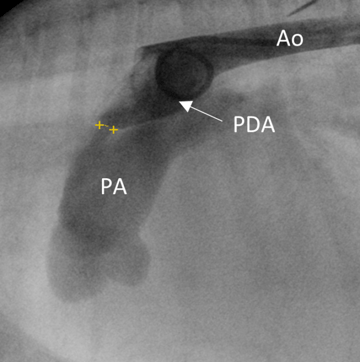

Step one: Vascular access is obtained via a surgical cut down to the right femoral artery, with the placement of a vascular introducer in the artery via a modified Seldinger technique. A pigtail catheter is then advanced to the level of the PDA under fluoroscopic guidance, and a bolus of radiopaque contrast is given. This produces an angiographic image of the ductus (Figure 4).

Step two: The minimal ductal diameter (MDD) describes the narrowest point where the PDA enters the pulmonary artery. It is measured via transthoracic echocardiography, transoesophageal echocardiography and/or angiographic study. This allows the selection of an appropriately sized ACDO device, in which the device “waist” is 1.5 to 2 times the measured MDD (yellow callipers in Figure 4).